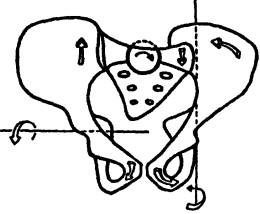

Ábra. 137. Kutatási szimmetrikus elrendezése a csípőlapátból

Ábra. 138. kismedencei eltolódás